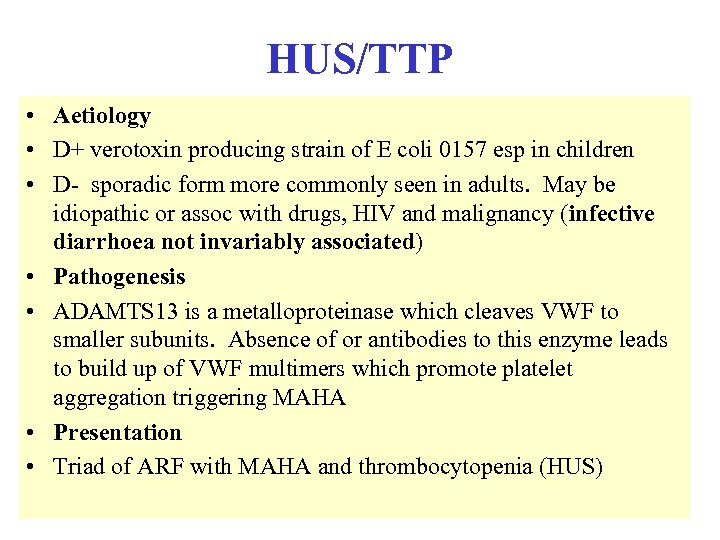

HUS/TTP • Aetiology • D+ verotoxin producing strain of E coli 0157 esp in children • D- sporadic form more commonly seen in adults. May be idiopathic or assoc with drugs, HIV and malignancy (infective diarrhoea not invariably associated) • Pathogenesis • ADAMTS 13 is a metalloproteinase which cleaves VWF to smaller subunits. Absence of or antibodies to this enzyme leads to build up of VWF multimers which promote platelet aggregation triggering MAHA • Presentation • Triad of ARF with MAHA and thrombocytopenia (HUS)

HUS/TTP • Aetiology • D+ verotoxin producing strain of E coli 0157 esp in children • D- sporadic form more commonly seen in adults. May be idiopathic or assoc with drugs, HIV and malignancy (infective diarrhoea not invariably associated) • Pathogenesis • ADAMTS 13 is a metalloproteinase which cleaves VWF to smaller subunits. Absence of or antibodies to this enzyme leads to build up of VWF multimers which promote platelet aggregation triggering MAHA • Presentation • Triad of ARF with MAHA and thrombocytopenia (HUS)

HUS/TTP • Differential diagnosis • HUS, MHT, scleroderma renal crisis and DIC can all cause same triad but clotting will be normal in first three and abnormal in DIC • Treatment • D+ supportive care only in children; PE with FFP in adults • D- daily PE and FFP in adults until no further haemolysis • Steroids may help idiopathic adult HUS/TTP if platelets do not increase after several days PE (steroids not of proven value) • Outcome • D+ usually make complete recovery (not usually fatal in kids) • D- up to 25% left with some renal impairment but long term dialysis not usually necessary. MI and heart failure are common

HUS/TTP • Differential diagnosis • HUS, MHT, scleroderma renal crisis and DIC can all cause same triad but clotting will be normal in first three and abnormal in DIC • Treatment • D+ supportive care only in children; PE with FFP in adults • D- daily PE and FFP in adults until no further haemolysis • Steroids may help idiopathic adult HUS/TTP if platelets do not increase after several days PE (steroids not of proven value) • Outcome • D+ usually make complete recovery (not usually fatal in kids) • D- up to 25% left with some renal impairment but long term dialysis not usually necessary. MI and heart failure are common